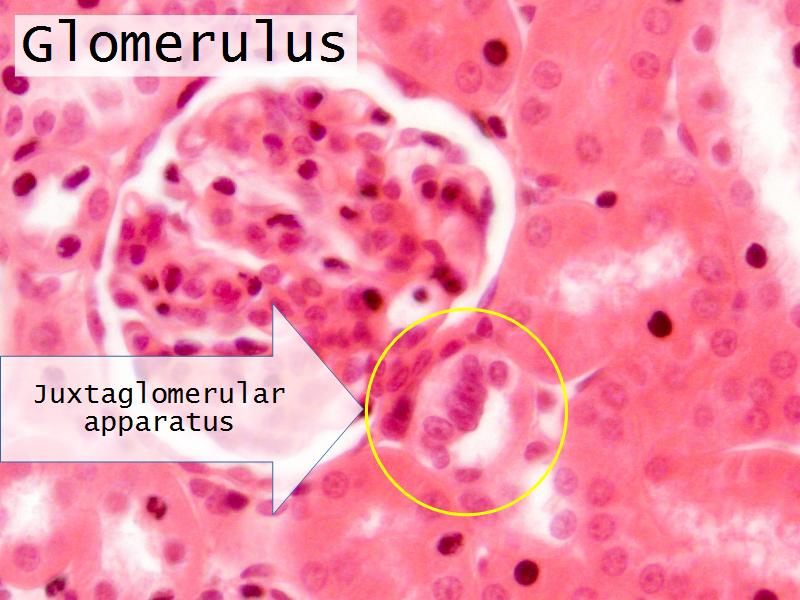

- Kidney

- Slide 76: Kidney

- Slide 84: Testis